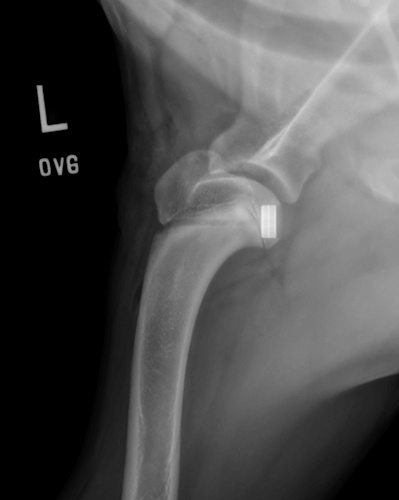

Coxofemoral Luxation (Hip Dislocation)

Hip Dislocation in canines

Treatment Option for Hip Dislocation

Post-op of a Hip Replacement